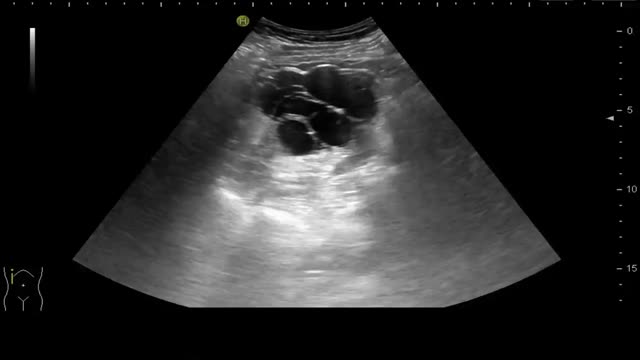

Ecográficamente las visualizamos como lesiones anecogénicas, redondeadas, de tamaño variable, de paredes finas y lisas, con refuerzo acústico posterior y sin contenido en su interior ni tabiques. Pueden ser corticales si dependen de la corteza renal o sinusales si se localizan en la zona medular10. Existen casos excepcionales en los que el quiste puede tener algún tabique en su interior, de mayor o menor grosor, con o sin contenido en su interior. Es en estas situaciones en las que hablamos de quistes complejos y es importante realizar una TAC para la correcta clasificación del quiste en la conocida como clasificación de Bosniak, que realmente es una clasificación radiológica de la TAC, no es una clasificación ecográfica (fig. 1 y video 1).

Imagen de la izquierda: Corte longitudinal y transversal en hipocondrio derecho. Quiste simple cortical de paredes finas, sin contenido, de unos 7cm. Imagen de la derecha: Corte longitudinal y transversal en hipocondrio derecho. Quiste cortical de paredes finas, con algún tabique fino en su interior.

A veces los quistes pueden sufrir una rotura espontánea o sangrado intraquístico, lo cual genera fiebre y dolor lumbar. En caso de complicación se observa una lesión con contenido ecogénico, bordes imprecisos, pérdida del refuerzo y a veces pérdida de la morfología redondeada habitual11,12.